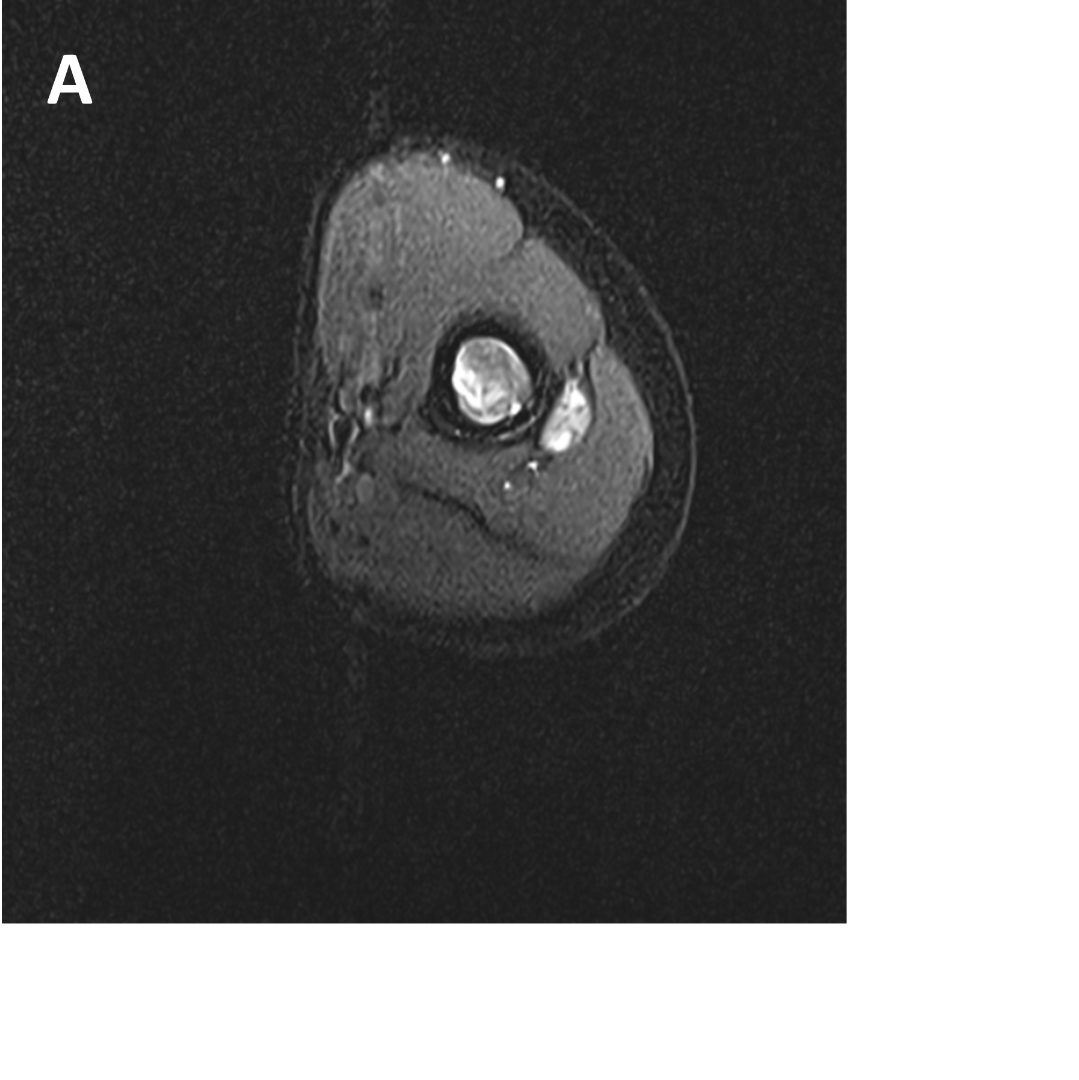

- (A,B) : MR LEFT FOREARM

- B 2 : Volume loss with fatty atrophy of brachioradialis, supinator, extensor carpi radialis longus and brevis muscles ,due to chronic denervation changes.